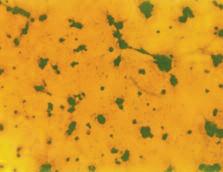

Nella pagina a fianco sono riportati gli incredibili risultati documentati per la prima volta in questo esperimento. Gli animali con carenza di vitamina C nella dieta sviluppano tumori di grandi dimensioni, che crescono sempre più diffusamente nei tessuti limitrofi (figura A). Al contrario, gli animali con una dieta ricca di vitamina C hanno sviluppato meno tumori e tumori più piccoli. Cosa ancor più importante, in questo gruppo un quantitativo ottimale di vitamina C nella dieta ha portato alla formazione di tessuto connettivo di confinamento (incapsulamenti) dei tumori (figura B). Questo esperimento dimostra che la presenza o l’assenza di vitamina C è un fattore decisivo per stimolare la difesa del corpo contro i danni del cancro.

AA. Un tumore cancerogeno sviluppato in un topo, non in grado di produrre vitamina C che viene sottoposto ad una dieta carente di vitamina C.

Notare che il confine diffuso del tumore (freccia) con le cellule tumorali che facilmente invade i tessuti circostanti

BB Con l’integrazione di vitamina C, i topi dello stesso esperimento hanno eretto una forte barriera di tessuto connettivo attorno al tumore, confinandolo alla posizione originale E' evidente da questa immagine che è improbabile che i tumori incapsulati invadano il tessuto circostante e creino una metastasi.